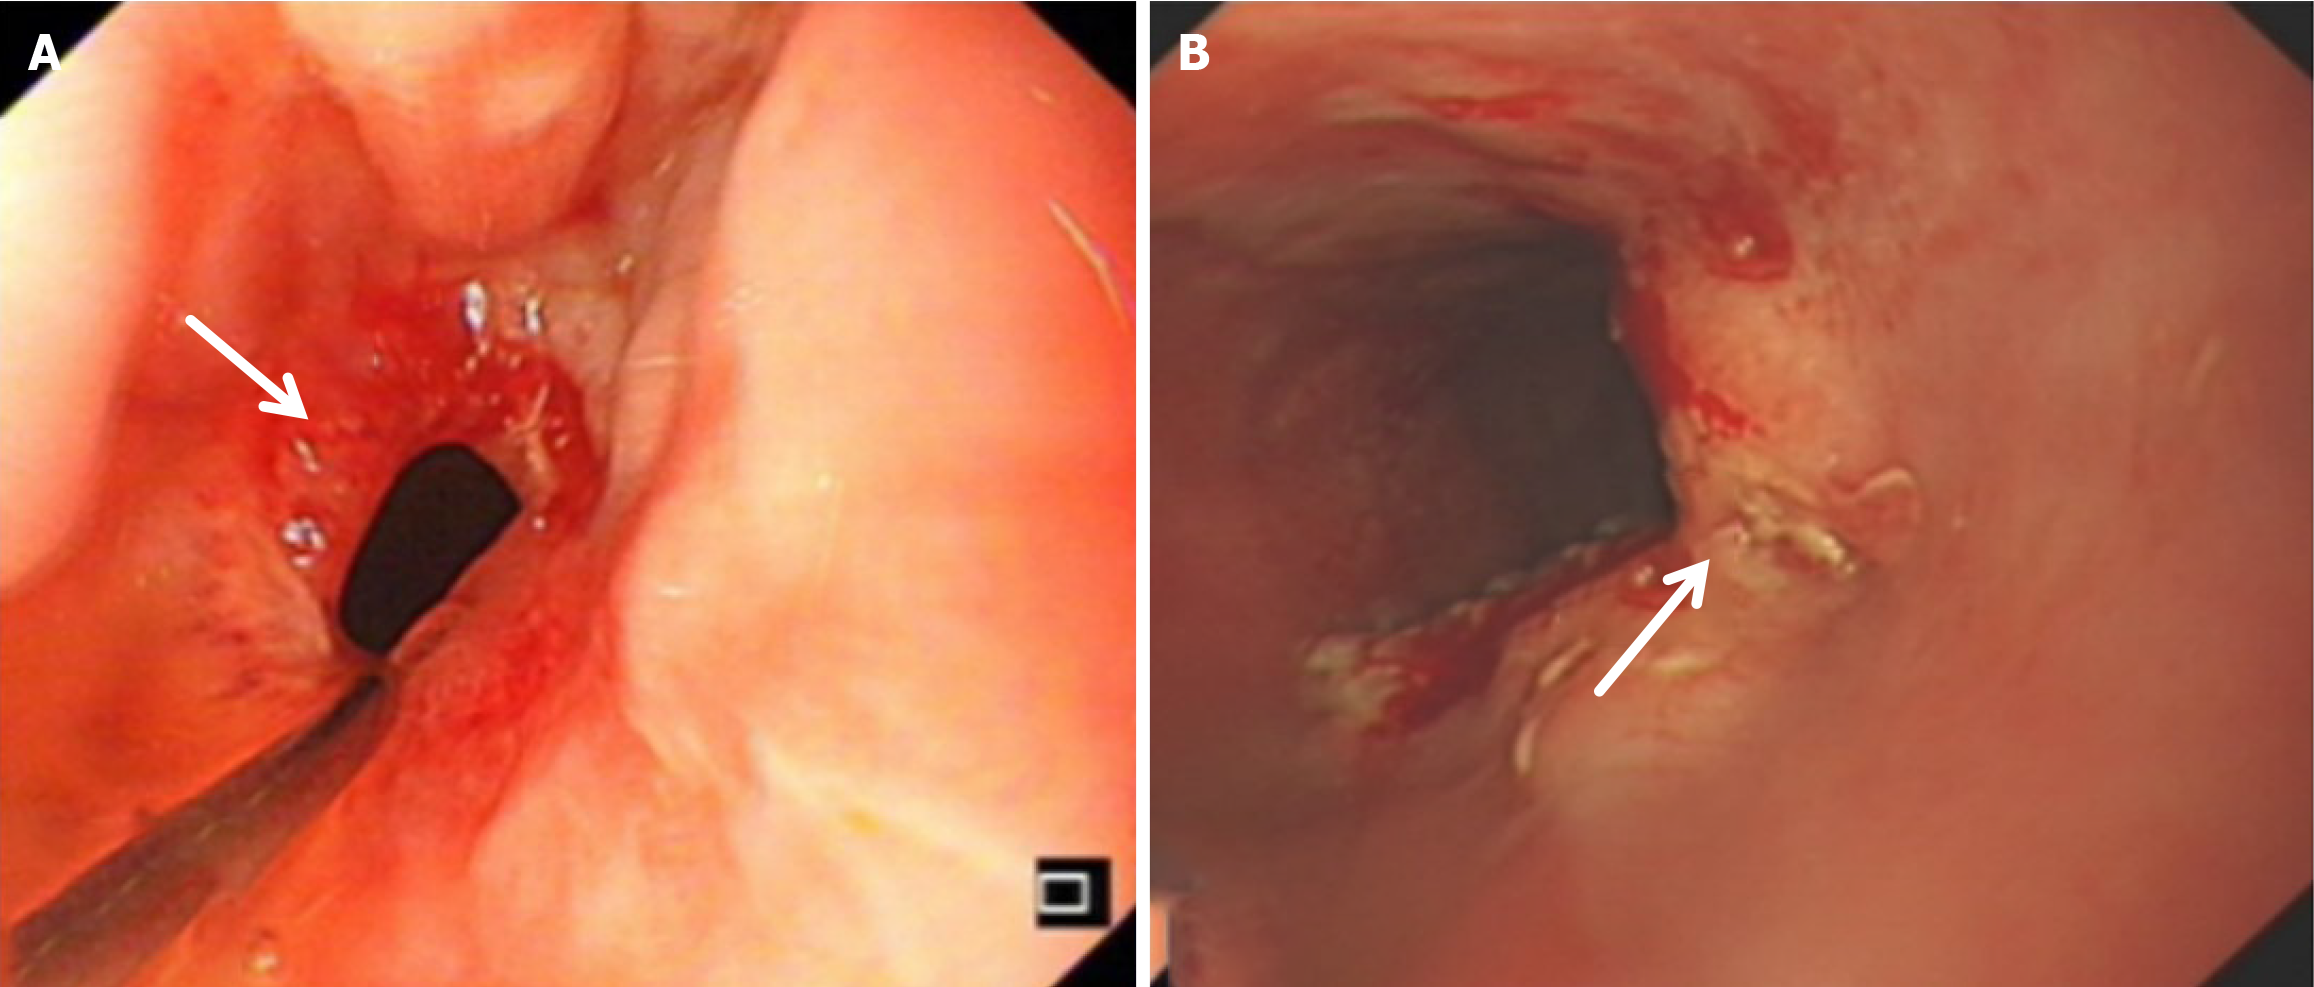

Compared with the modified group, the Orr group had a greater incidence of anastomotic leakage (AL) and short-term complications of anastomotic ischemia, although there was no significant difference between the two groups. Furthermore, Fisher’s exact probability analysis revealed that the incidence of reflux esophagitis, anastomotic ulcers by endoscopic examination, and intestinal obstruction in the Orr group was greater than that in the modified group at the 6-month postoperative follow-up period (P < 0.05) (Tables 3, 4 and 5).

There was no significant difference in weight loss between the two groups at 1 month after the operation (P > 0.05). However, in the improved group, the weight of the improved group was less than that of the original group at 3 months and 6 months after the operation (P < 0.05). The hemoglobin in the Orr group decreased significantly at 1 and 3 months after the operation compared with that in the improved group (P < 0.05), but there was no significant difference between the two groups at 6 months after the operation (P > 0.05). There was no significant difference in total protein or serum albumin between the two groups at 1 month, 3 months, and 6 months after the operation (P > 0.05) (Figures 2, 3, 4, 5 and 6, Table 6).

After total gastrectomy, due to the loss of antireflux function of the cardia, the reverse peristaltic wave generated by the pacing cells of the duodenum leads to the reflux of food and bile into the esophagus, resulting in clinical symptoms such as reflux esophagitis and other gastrointestinal duct discomfort[21]. Previous studies have shown that the jejunal storage bag after total gastrectomy can effectively relieve the pressure of food passing through the esophagojejunostomy. When food flows back from the distal output loop, the storage bag has a similar “siphon effect” to play an antireflux role and reduce the incidence of reflux esophagitis[22]. The antireflux effect is positively proportional to the length of the jejunal storage bag; nevertheless, a storage bag that is too long increases the incidence of Roux stasis syndrome, and the ideal length is approximately 5 cm[23]. In our study, storage bags with a length of approximately 5 cm were constructed at the anastomosis of the esophagus and jejunum in both groups. Our results revealed that the incidence of reflux esophagitis in the Orr group was greater than that in the improved group (P < 0.05), which occurred because the jejunal storage bag was constructed after the jejunum and its mesentery were disconnected, and the residual end of the storage bag lacked traction of the mesentery in the Orr group; therefore, the “siphon effect” was weakened. By contrast, the storage bag of patients in the improved group only needed to disconnect the jejunum, and the jejunal mesentery was continuous, resulting in strong negative pressure suction.